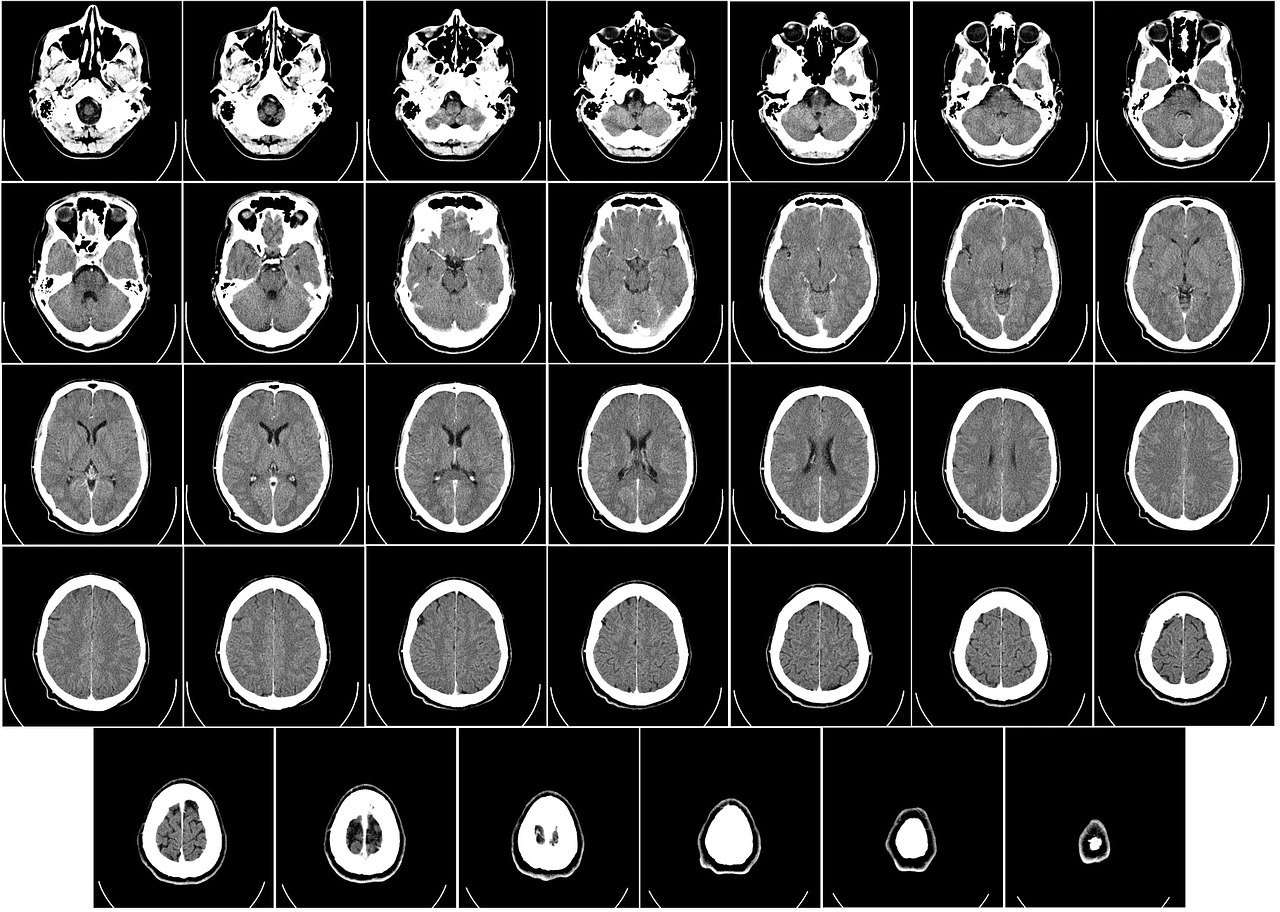

CT 및 CT 혈관조영술(CTA):

CT는 급성 뇌출혈이나 뇌경색 평가에 유용하며, CTA를 통해 혈관의 협착 부위를 확인할 수 있습니다. 모야모야병의 경우, CT 상에서도 내경동맥 말단부의 협착과 우회 혈관 형성이 관찰될 수 있으나, MRA와 DSA에 비해 세부적인 혈관 소견은 다소 부족할 수 있습니다.